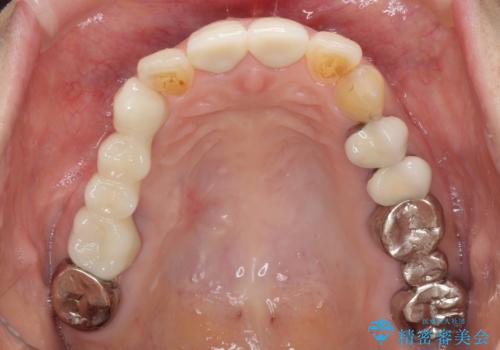

- 歯肉が退縮したためにクラウンの縁や歯根が見えてしまっていることを気にして来院された患者様です。

仮歯に変えた後にオールセラミッククラウンにて補綴することとしました。

強い咬合力や磨きすぎなどにより、歯根が見えてしまったり、金属の縁が見えてしまったりし、審美障害を引き起こすことがあります。

歯根が変色してしまうと、歯肉越しに歯根の黒い色が透けてしまうことがあり、この点についてはどうにも施しようがないため、患者様には事前のご理解いただきました。